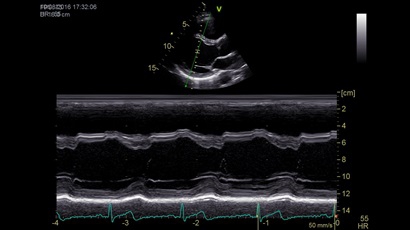

Анатомический М-режим:

Да

M-режим:

• Режимы: 4D, 2D (B-режим), цветной допплеровский режим, режим энергетического допплера, M-режим, цветной M-режим, спектральные режимы импульсно-волнового допплера (PW) и непрерывно-волнового допплера (CW), визуализация скорости движения тканей.